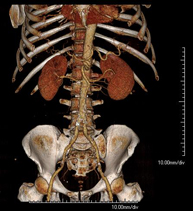

- Abdomen y pelvis- TC Abdomen Prueba diagnóstica que consiste en obtener imágenes del abdomen de alta definición anatómica (hígado, vesícula biliar, vía biliar, páncreas, bazo, estómago, intestinos, riñones, estructuras vasculares, vejiga, útero y ovarios, etc.) mediante el empleo de un equipo de TC (Tomografía Computarizada). Dichas imágenes se estudian posteriormente en una estación de trabajo que permite reconstrucciones bidimensionales en diferentes planos del espacio, y también reconstrucciones 3D (volumétricas). La mayoría de estudios requieren el empleo de contraste yodado para mejorar la definición de las imágenes. Prueba diagnóstica que consiste en obtener imágenes del abdomen de alta definición anatómica (hígado, vesícula biliar, vía biliar, páncreas, bazo, estómago, intestinos, riñones, estructuras vasculares, vejiga, útero y ovarios, etc.) mediante el empleo de un equipo de TC (Tomografía Computarizada). Dichas imágenes se estudian posteriormente en una estación de trabajo que permite reconstrucciones bidimensionales en diferentes planos del espacio, y también reconstrucciones 3D (volumétricas). La mayoría de estudios requieren el empleo de contraste yodado para mejorar la definición de las imágenes.

- TC Abdominopélvico Prueba diagnóstica que consiste en obtener imágenes bi y tridimensionales del abdomen y de la pelvis de alta definición anatómica (estructuras óseas, estructuras vasculares, hígado, páncreas, vesícula biliar, riñones, glándulas suprarrenales, bazo, intestino delgado y grueso, vejiga, útero y ovarios, próstata y vesículas seminales, uréteres, etc.) mediante el empleo de un equipo de TC (Tomografía Computarizada). La mayoría de estudios requieren el empleo de contraste yodado. Prueba diagnóstica que consiste en obtener imágenes bi y tridimensionales del abdomen y de la pelvis de alta definición anatómica (estructuras óseas, estructuras vasculares, hígado, páncreas, vesícula biliar, riñones, glándulas suprarrenales, bazo, intestino delgado y grueso, vejiga, útero y ovarios, próstata y vesículas seminales, uréteres, etc.) mediante el empleo de un equipo de TC (Tomografía Computarizada). La mayoría de estudios requieren el empleo de contraste yodado.